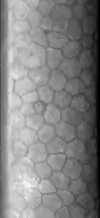

L’endothélium cornéen est une mono-couche cellulaire formant une mosaïque hexagonale. Ses cellules ne se régénèrent pas.